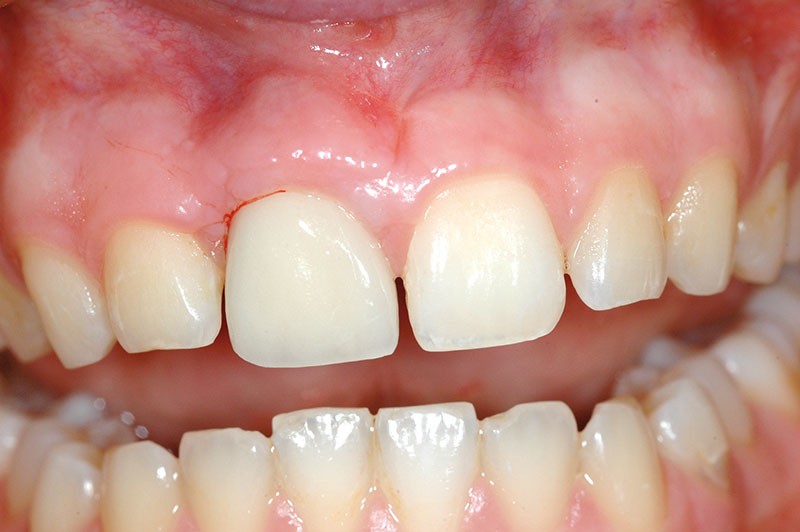

Une patiente âgée de 28 ans consulte pour un problème esthétique au niveau de la dent 11, porteuse d’une couronne implanto-portée (fig. 1a).

L’examen clinique révèle une différence d’alignement et un tissu gingival péri-implantaire peu épais sur cette couronne implanto-portée.